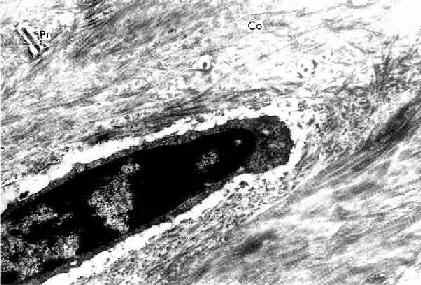

(1)骨细胞(osteocyte):单个分散于骨板内或骨板间。骨细胞是有许多细长突起的细胞,胞体较小,呈扁椭圆形,其所在空隙称骨陷窝(bone lacuna),突起所在的空隙称骨小管(bone canaliculi)(图4-6)。相邻骨细胞的突起以缝隙连接相连,骨小管则彼此连通。骨陷窝和骨小管内含组织液,可营养骨细胞和输送代谢产物(图4-7)。骨陷窝周围的薄层骨基质钙化程度较低,并可不断更新,在机体需要时,骨细胞的溶骨作用可溶解此层骨基质,使Ca2+释放入骨陷窝的组织液中,继而进入血液,对维持血钙的恒态水平有一定作用。

图4-6 小鼠骨细胞和骨基质(脱钙后)电镜像×25000

Pr骨细胞突起和骨小管,Co胶原原纤维

(上海医科大学电镜室供图)